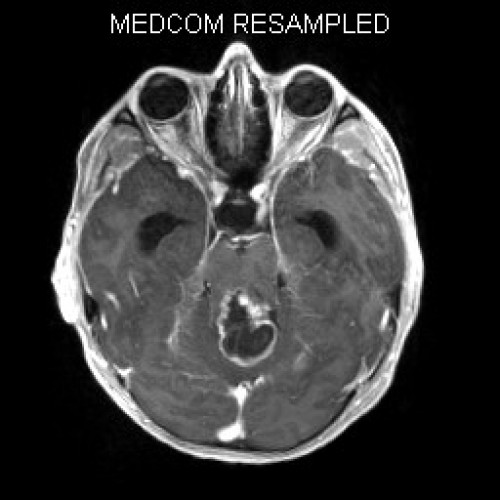

Müdigkeit und schlechte Noten

Fall-ID: 592

ICD: C75.3

ICD: G91.9

12-jähriger Junge. Die Eltern werden zu einem Gespräch bei der Klassenlehrerin gebeten, weil ihr Sohn sehr unaufmerksam geworden sei und seine Leistungen in der Schule bedenklich abgenommen hätten. Er droht das Klassenziel der 6. Klasse nicht zu erreichen.

Den Eltern war seit längerer Zeit bereits aufgefallen, dass sich ihr Sohn nach der Schule am liebsten ins Bett lege, um für eine Stunde einen Mittagsschlaf zu halten.